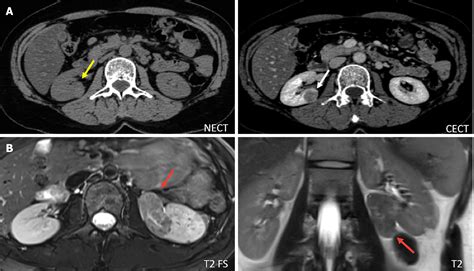

The diagnosis of an angiomyolipoma of the kidney relies heavily on medical imaging. Because these tumors contain macroscopic fat, they have a very distinct appearance on radiology scans. Radiologists use the following tools to identify them:

• Computed Tomography (CT) Scan: The gold standard for diagnosis. The presence of fat density within a kidney lesion is a hallmark of an angiomyolipoma.

• Magnetic Resonance Imaging (MRI): Useful for patients who cannot undergo CT scans or to further characterize the tumor composition.